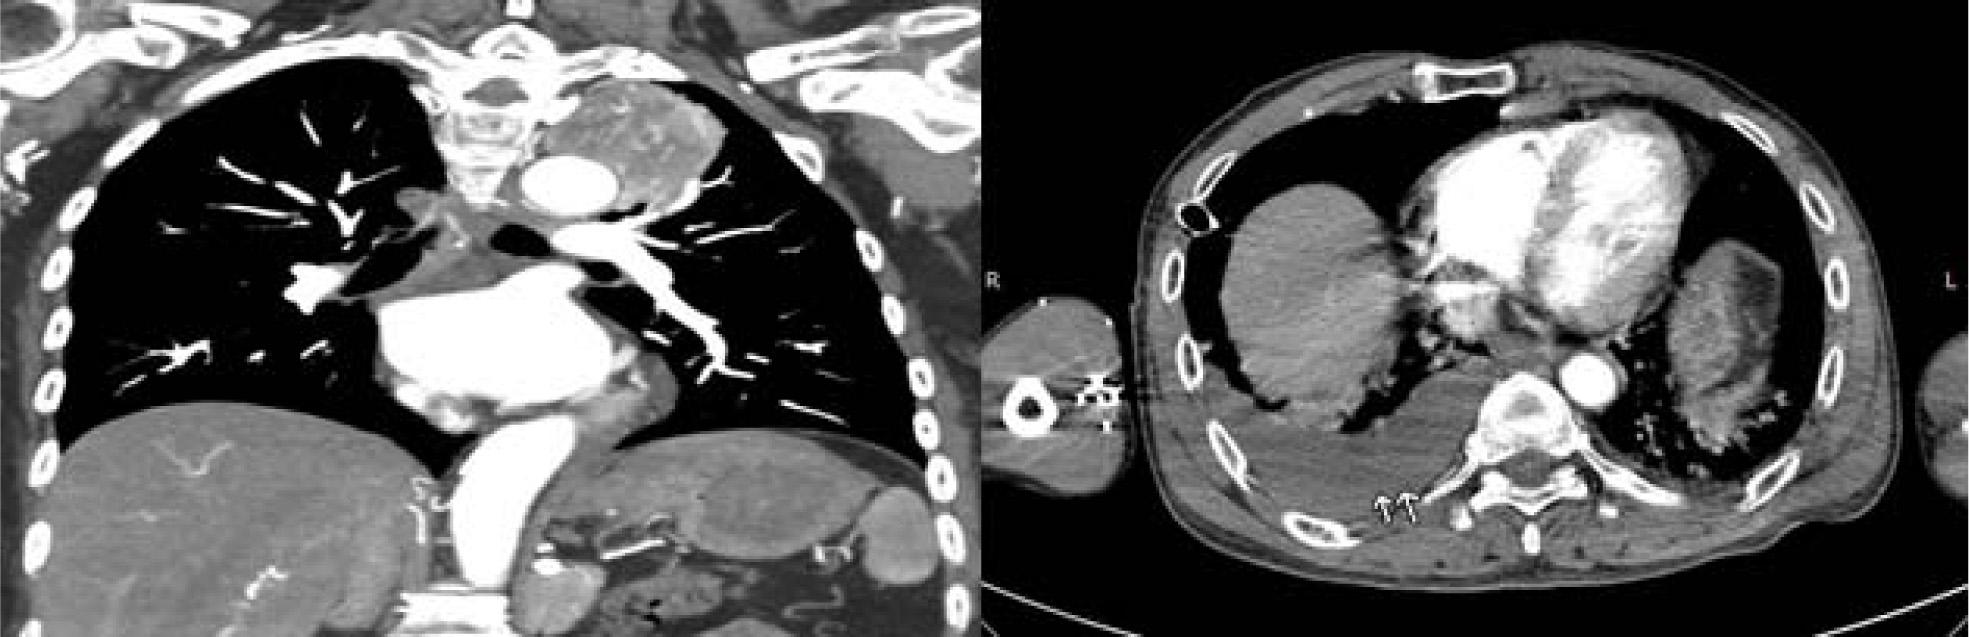

Figure 2